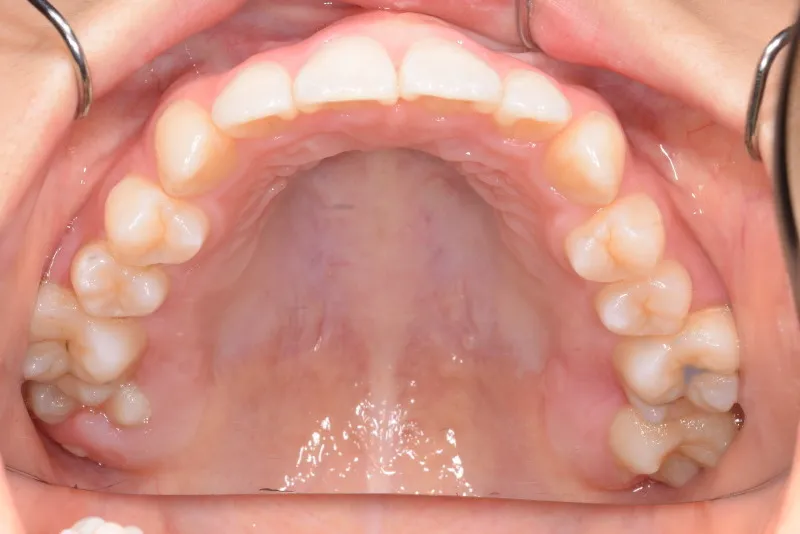

治療終了後

治療回数48回、7年2ヶ月の治療期間で矯正治療を終了しました。

主訴が改善され、ご満足頂きました。